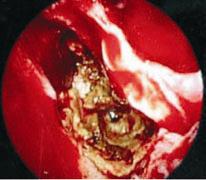

其實黴菌性鼻竇炎分為兩大類,其中一類是屬於侵襲性的黴菌性鼻竇炎,這種黴菌性鼻竇炎少見,特徵就是黴菌會入侵鼻部黏膜以及血管並且很快漫延到附近的重要器官,有相當高的致死率,主要發生在免疫力相當低的患者身上,例如接受化學治療後免疫力下降或接受骨髓移植的癌症病人,亦或是年紀大血糖控制不良的糖尿病患者,這類病人大概都出現在醫學中心裡。另外一類是屬於非侵襲性的黴菌性鼻竇炎(圖二),絕大多數人得到的黴菌性鼻竇炎屬於這類型,這是免疫力正常的人也可能會得到的疾病,症狀常常有單側的鼻塞、鼻水倒流、鼻腔有臭味(魚腥味)、頭痛或者甚至有鼻涕帶血絲,有部分病人同時伴隨有細菌性的感染則會有黃膿鼻涕。

圖二、內視鏡手術中將上頷竇打開可見鼻竇內充滿褐黃色黴菌塊(A),以及取下後的黴菌塊(B)

56歲鄭女士過去數年間,左側時常有黃色濃稠的鼻涕並偶爾會聞到「魚腥味」,也覺得左側鼻塞持續了一年多,在診所求助了好幾位耳鼻喉科醫師,得到的答案都是「鼻竇炎」。先吃藥治療,從第一代抗生素吃到第三代,但是症狀仍是沒有改善,於是來到大醫院求診。鼻竇的X光顯示左側上頷竇的區域顯現白濁的現象,於是安排了鼻竇的電腦斷層檢查,顯現出左側上頷竇填滿了軟組織樣的物質,後來患者接受了左側功能性鼻竇內視鏡手術,在左側上頷竇發現塞滿了黑黑黃黃易碎的塊狀物(黴菌塊),配合使用微創手術的器械以及「鼻竇微創水刀」將之清除乾淨,並仔細檢視確定沒有殘留的黴菌。術後患者定期於門診追蹤,鼻竇內視鏡檢查顯示並無黴菌感染復發。